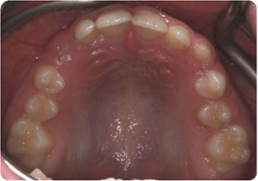

Each case shows the front view and an arch or side view, before and after BioLign Method-guided treatment.

All cases treated within 6–12 months.

Overlapping teeth resolved through arch form restoration